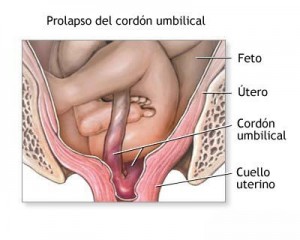

PROLAPSO DEL CORDON UMBILICAL

Es una condición durante las útimas etapas de embarazo en las que el cordón umbilical desciende dentro de la vagina prematuramente; con más frecuencia después que las membranas se han roto y el bebé se mueve dentro del canal de parto para el alumbramiento.